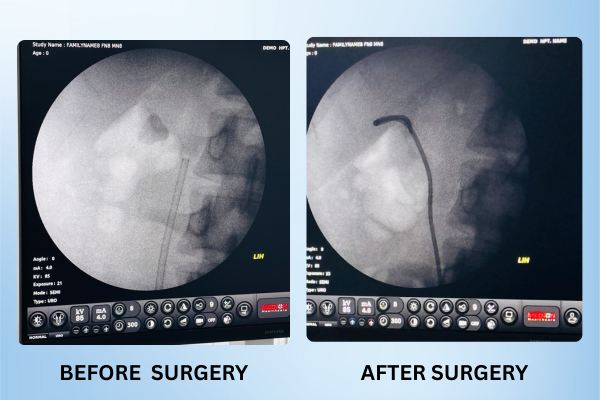

Giant Ureteric Stone Removal

Complex Ureteric Stone Cleared

A challenging upper ureteric stone near the spine was removed using laser surgery. The patient was discharged the next day without any complications and with fully restored kidney function.